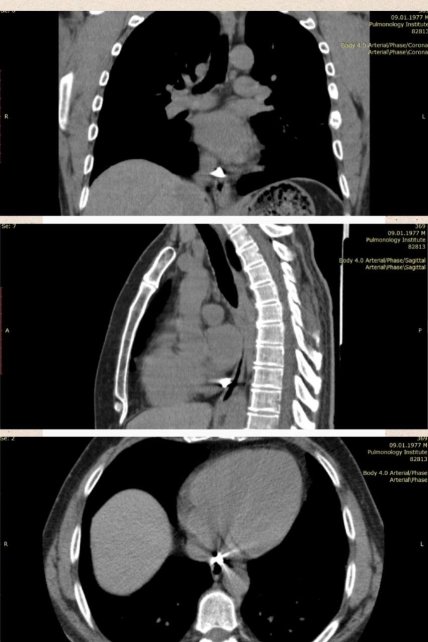

Фахівці провели КТ дослідження та виявили у чоловіка в перикарді (зовнішня сполучнотканинна оболонка серця) металевий уламок значних розмірів – 8 на 9 міліметрів.

Специфічне розташування осколка ускладнювало оперативне втручання та було вирішено провести мініінвазивне торакоскопічне видалення уламка із застосуванням спеціального магніту. Пацієнту зробили невеликий надріз у грудній стінці та витягли звідти стороннє тіло.